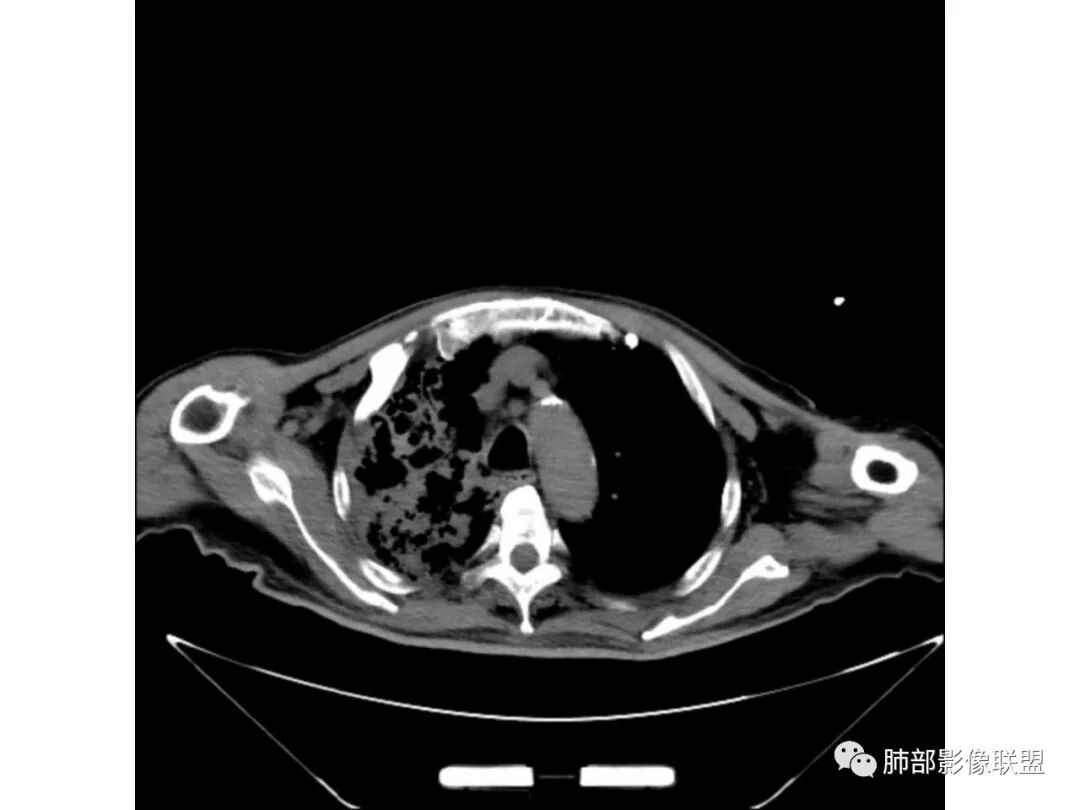

老年男性,既往糖尿病10年,右上肺不均匀实变+两肺实质及间质病变;本例良性感染性病变支持点:糖尿病史+双肺多发的实变,右上肺实变内可见支气管气像;恶性支持点:实变内的支气管似乎呈“枯树枝”样改变,纵隔有超过1.5cm的肿大淋巴结。

个人倾向良性感染性病变>恶性;考虑双肺混合性感染,右肺上叶实变拟结核可能性大,重点鉴别是弥漫浸润性肺腺癌。建议纤支镜检查。

老年男性,咳嗽气喘10天,双肺明显肺气肿,右上肺叶实变,内见大量空洞及囊腔样改变(部分为支气管扩张),实变区周围表现为网格样改变,有明显的小叶间隔增厚,边界似清非清,支气管走行僵硬,有枯树枝样改变,双下肺胸膜下小叶间隔增厚明显,边缘相对模糊,综合考虑如下:1、粘液腺癌可能大(枯树枝样改变,边界似清非清,小叶间隔增厚符合)。2、结核,右上肺似像干酷样改变,内有空洞及支扩样改变支持,但下肺及左肺无相关支气管播散的小叶中心结节及树芽,不支持,临床病症不支持,只有咳嗽,喘气,无咳痰及结核中毒症状。当然结核是妖,需要结合痰检及结核相关指标进一步明确。3、肺克,虽有10年糖尿病史,但肺部只有右肺改变明显,无胸膜下脓肿表现,无脓毒栓表现,临床症状也不支持。4、其他感染?双下肺胸膜下病灶边缘模糊,不完全除外,需要结合临床炎性指标分析。

右上肺大片状高密度影,呈蜂窝样改变,部分气腔无壁,部分呈厚壁改变,内部结构紊乱,部分边缘GGO边界清楚,大小不一,病灶近端小远端大,近端支气管壁增厚,支持感染性病变,考虑结核,其内支气管呈枯树枝改变,病灶局部膨隆,内部结构紊乱,边界的GGO部分清楚,恶性(腺癌)待排。

3、增强扫描很重要,增强后,结核的坏死很彻底,很少异常强化,(鳞癌也类同)。而粘液腺癌血管常显影,有时是毛糙的,整体密度偏低,哟其实纵膈窗。